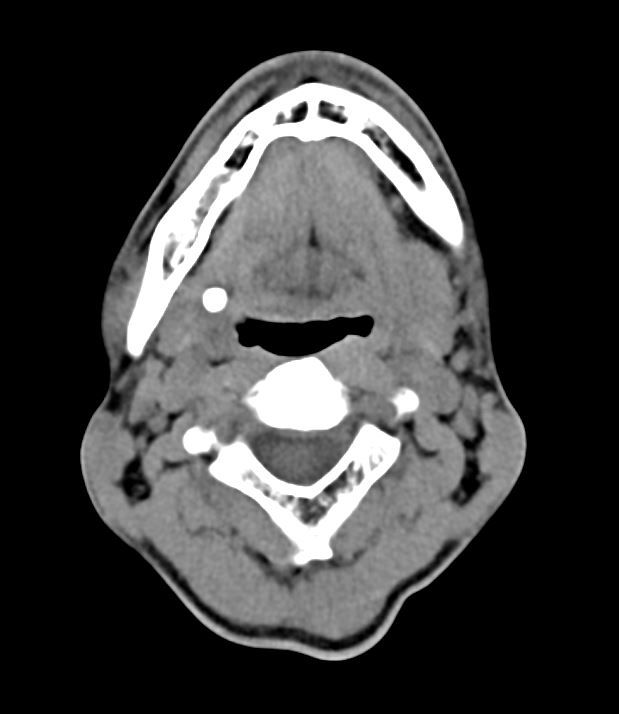

오랜기간 오른쪽 턱밑 타석증으로 인해 침샘이 많이 위축됐따고 합니다

2차병원 이비인후과 교수 말로는 타석증으로 인한 침샘염때문에 경동맥 쪽이 부을순 있는데

• 2번 째 사진